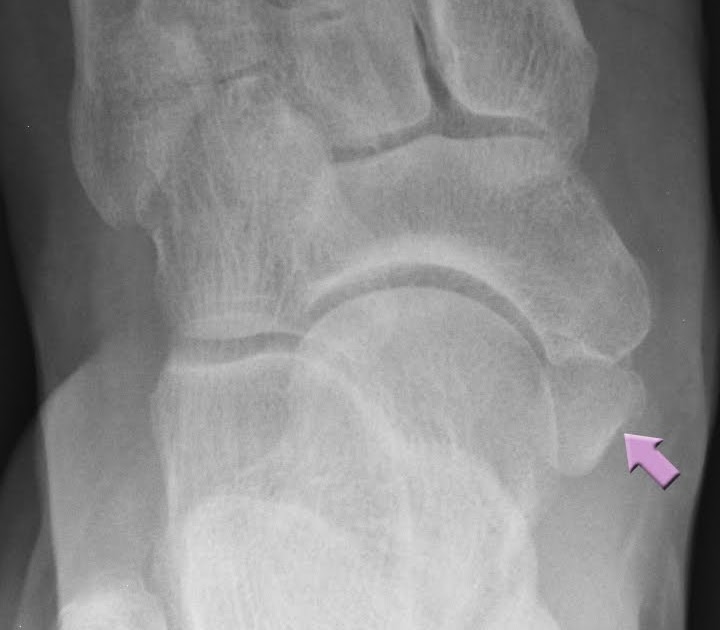

Accessory navicular bone on plain Xray in 5 cases; case 1 (type II Accessory Navicular Bone Types — the accessory navicular bone (anb) is one of the most common accessory bones in the foot. Type 1 accessory navicular bone: Type 2 is larger and connects to the navicular via a cartilage bridge (called a synchondrosis). It is not connected to the navicular bone. Type 3 is the most prominent and connects to the navicular via a. Accessory Navicular Bone Types.